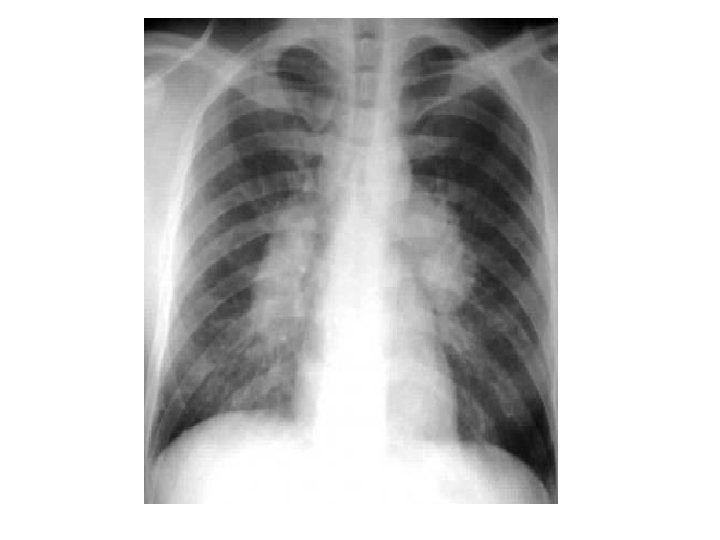

Thimble Bladder • Markedly contracted and small capacity urinary bladder, with diffuse asymmetric bladder wall thickening. Proximal hydroureteronephrosis is seen bilaterally.